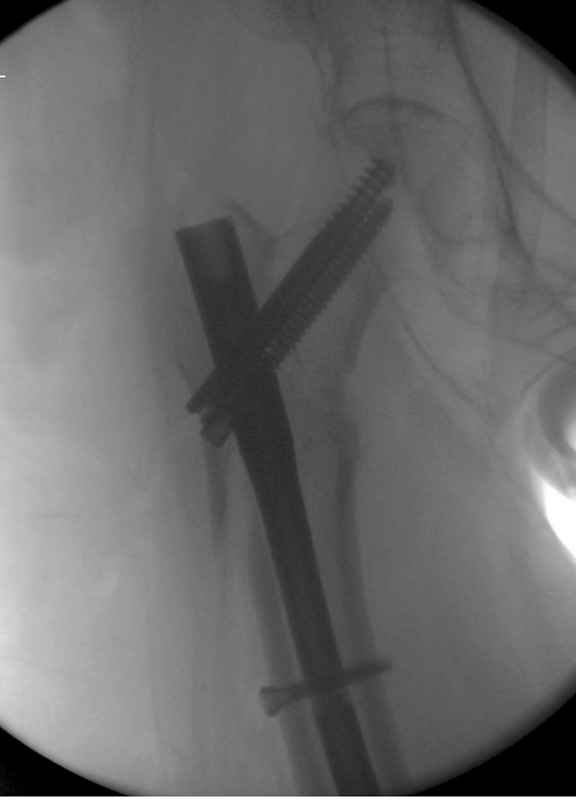

Здесь 83 года, травма в результате падения

Djoldas Kuldjanov, M.D.

Department of Orthopedic Surgery

St. Louis University